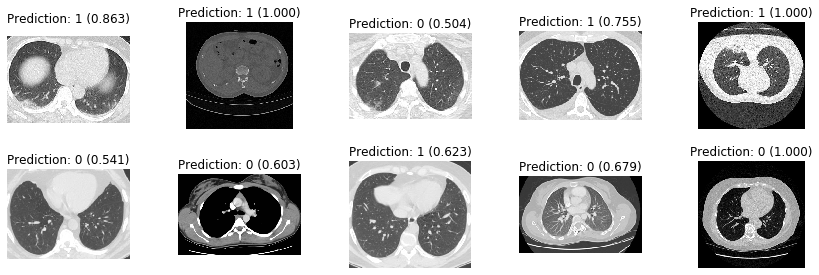

10エポックほど回してテストデータを分類した結果は以下のとおりです。上段はCOVID-19が陽性(ラベル1)、下段は陰性(ラベル0) です。画像の上に推定結果と確率を示しています。素人目には何が何だか分からないですが、予測が結構あたっています。